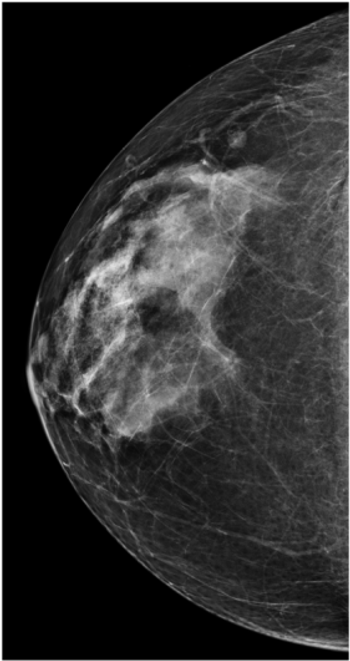

Follicular LymphomaByThomas Cade Raggio, MD,Erini Makariou, MDNovember 23rd 2011An 84-year-old female presents for asymptomatic screening mammogram. Craniocaudal and MLO views of the right breast on demonstrate stable appearance of an intramammary lymph node in the upper outer quadrant.